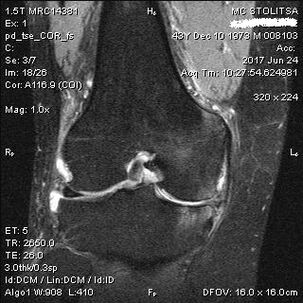

Põlveliigese artroosi diagnoosimine ja ravi

Põlveliigese artroosi diagnoosimine toimub reumatoloogi või ortopeedi kabinetis. Arst vaatab kahjustatud liigese üle, palpeerib seda, kuulab ära kaebused ja esitab lisaküsimusi. Teeb mitmeid katseid – näiteks palub patsiendil jalga painutada või paar sammu kõndida. Seejärel, kui on vaja selgitada haiguse staadiumi või patoloogiliste muutuste olemust, suunab ta teid täiendavatele uuringutele. Näiteks kompuutertomograafia või radiograafia jaoks.